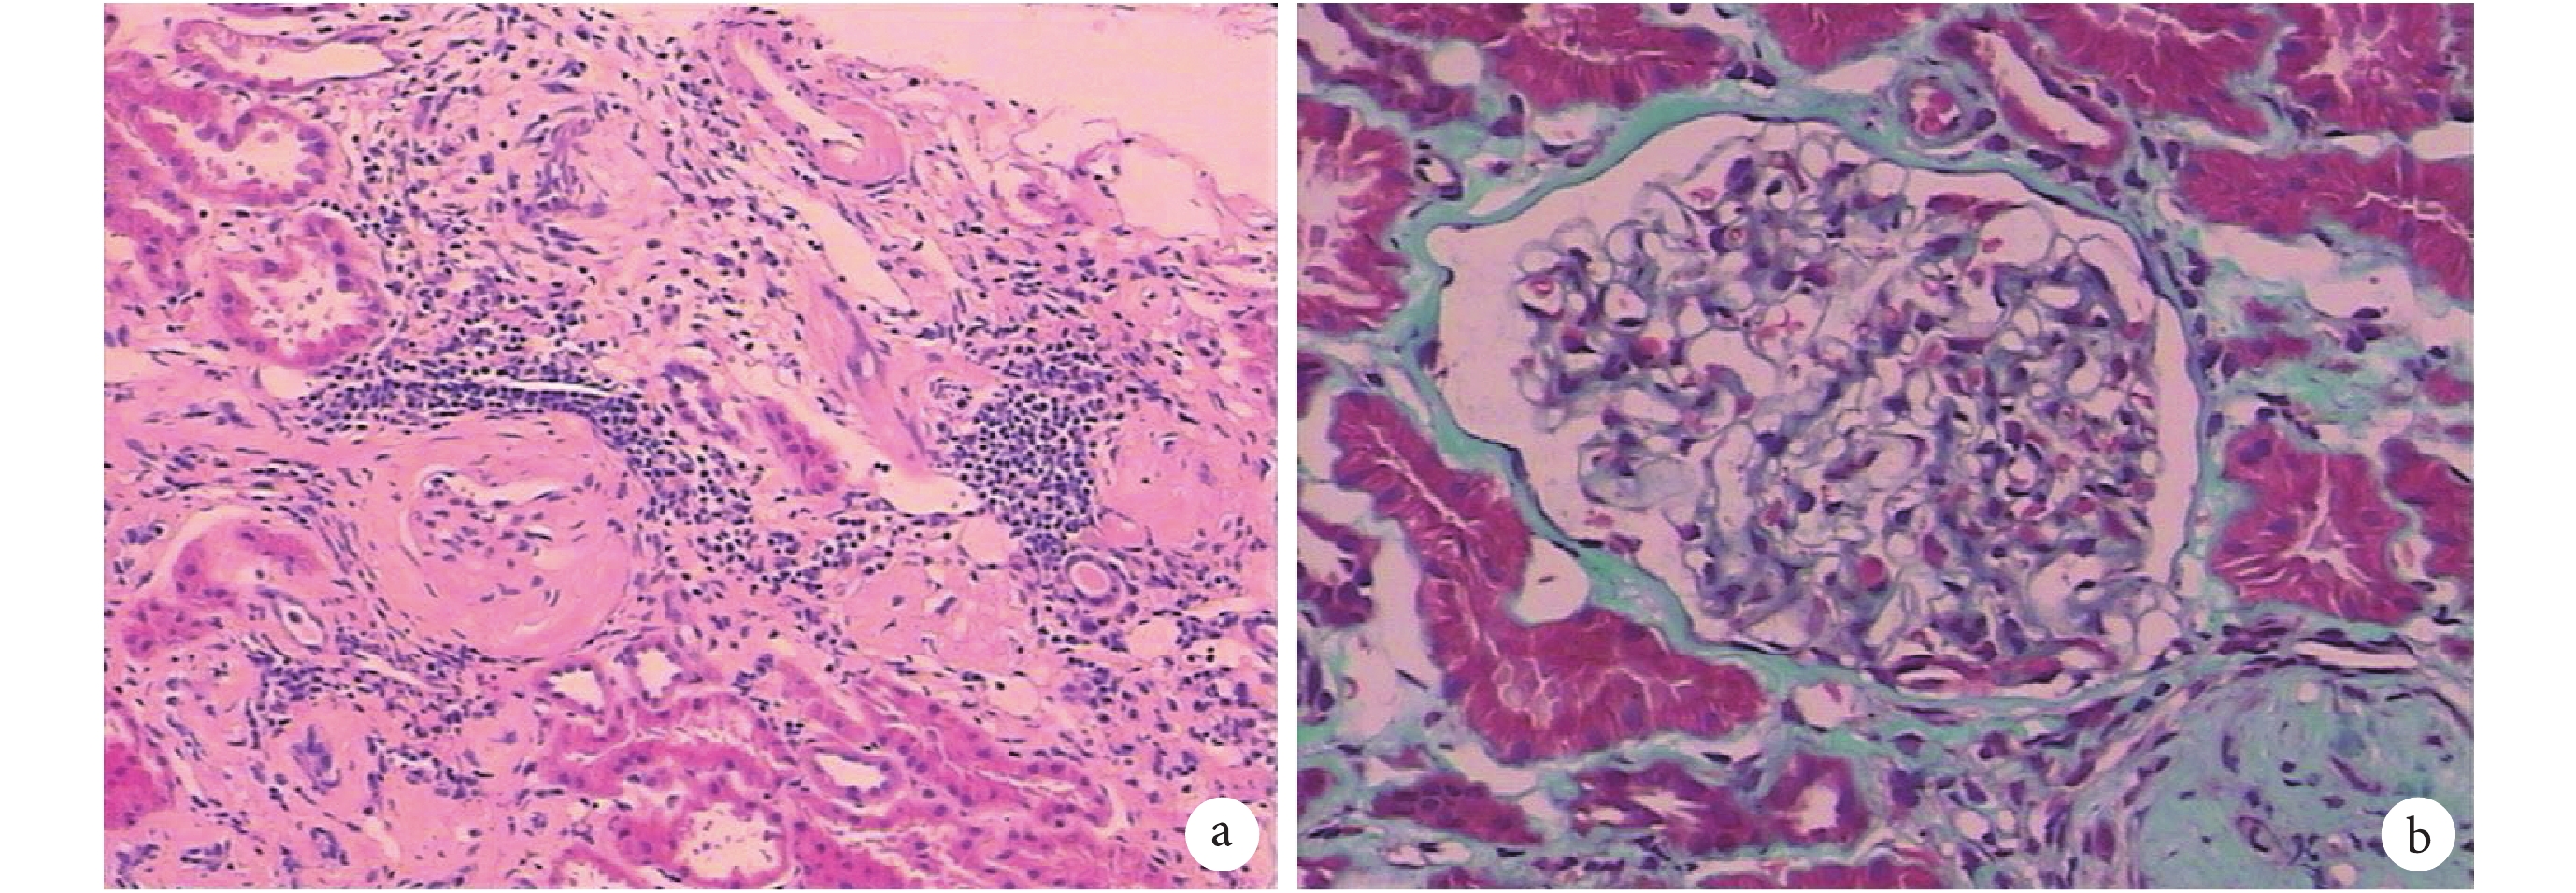

a. 可見腎小管萎縮,小管上皮細胞輕度變性,同時可看到硬化的腎小球及淋巴細胞的浸潤(HE ×10);b. 可見系膜節段或球性細胞及基質輕度增生,基膜節段空泡變性,小動脈壁輕度增厚(HE ×40)

病例介紹 患者,女,52 歲。于 2016 年 4 月 5 日因“發現肝功能異常 2 年,尿液檢查異常 4+ 個月”入住四川大學華西醫院。既往體健,無結核、肝炎等傳染病病史,無糖尿病、高血壓等病史。10 余年前于當地醫院行“右側卵巢囊腫切除手術”,患者無吸煙、飲酒、放射物及毒物接觸史。2 年前(2014 年 4 月)患者因治療“霉菌性陰道炎”服用氟康唑后出現尿黃、面色發黃癥狀就診于當地醫院,肝功能檢查:丙氨酸氨基轉移酶(alanine aminotransferase,ALT)1 939 U/L,天門冬氨酸氨基轉移酶 (alanine transnminase,AST)683 U/L,直接膽紅素/總膽紅素(direct bilirubin/total bilirubin,BILD/T)70/114 μmol/L,診斷不詳,給予保肝、退黃治療(具體藥物名稱及劑量不詳)后就診于四川大學華西醫院,該院考慮患者因治療“霉菌性陰道炎”服用氟康唑后出現尿黃、面黃等不適,且患者肝酶水平升高,診斷為“藥物性肝損害”(未行肝臟穿刺),給予保肝、降酶、退黃等對癥治療后患者于 2014 年 5 月 10 日出院。出院后反復出現肝臟酶學增高,在當地醫院進行免疫自身抗體檢查示:抗核抗體(antinuclear factor,ANA)核均質并核顆粒型(1∶100)、抗平滑肌抗體(anti-smooth muscle antibody,SMA)1∶320,免疫球蛋白(immunoglobulin,Ig)G 19.53 g/L(7.23~16.60 g/L),血清蛋白電泳示:γ 球蛋白 36.9%(13.1%~23.3%),EB 病毒,巨細胞病毒,甲、乙、丙、丁、戊型肝炎病毒均為陰性;腹部超聲及肝臟增強 MRI 檢查示:肝實質彌漫性損害(肝硬化)、脾大、腹水;肝穿刺病理切片會診示:自身免疫性肝炎(autoimmune hepatitis,AIH),不除外重疊藥物性肝損傷,病變程度相當于 G3S3,即炎癥 3 級纖維化 3 期,免疫組織化學檢查:乙肝表面抗原(–),肝組織多發性骨髓瘤癌基因-1(易見陽性細胞);膽管標志物細胞角蛋白 7、19 示小膽管增生。給予患者甲潑尼龍(48 mg,1 次/d)口服治療并逐漸減量至 16 mg 進行長期維持治療。在當地醫院住院期間發現尿隱血(+++),尿蛋白(+),肌酐 132 μmol/L(53~97 μmol/L),為明確腎臟問題于 2016 年 4 月 5 日入住四川大學華西醫院腎臟內科。體格檢查:體溫 36.6℃,脈搏 112 次/min,呼吸頻率 20 次/min,血壓 127/83 mm Hg(1 mm Hg=0.133 kPa)。面色晦暗,皮膚鞏膜輕度黃染,全身淺表淋巴結未捫及腫大,肝掌陽性,蜘蛛痣陰性,頸靜脈無怒張,心肺體格檢查未見明顯異常,全腹軟,腹壁未見靜脈曲張,無壓痛及反跳痛,肝、脾肋下未觸及,雙腎未觸及,雙下肢輕度凹陷性水腫。血常規檢查示:血紅蛋白 135 g/L,血小板計數 91×109/L,白細胞計數 10.05×109/L;尿常規檢查示:尿蛋白(+),隱血(+),紅細胞 246 /HP;尿白蛋白/肌酐 512.3 mg/g;24 h 尿蛋白量 0.99 g;腎功能檢查示:尿素 5.40 mmol/L,肌酐 77.0 μmol/L,估算腎小球濾過率 77.27 mL/min,尿酸 502 μmol/L;肝功能檢查示:ALT 19 U/L,AST 94 U/L,BILD/T 6.5/14.4 μmol/L,堿性磷酸酶 151 U/L,谷氨酰轉肽酶 69 U/L;AIH 相關抗體未見明顯異常;血清蛋白電泳 γ-球蛋白、α1-球蛋白等均未見明顯異常;免疫自身抗體檢查示:ANA 核均質并核顆粒型(1∶100),抗中性粒細胞胞漿抗體(anti-neutrophilcy- toplasmic antibodies,ANCA)、抗腎小球基底膜抗體未見異常;Ig 未見明顯異常。雙腎超聲檢查示:右腎大小約 10.0 cm×4.5 cm×3.8 cm,左腎大小約 11.5 cm×4.7 cm×5.1 cm,雙腎實質回聲稍增強,集合系統未見明顯分離暗區及強回聲團。腎穿刺活體組織檢查(活檢)(圖 1a、1b)示:光學顯微鏡下 ① 腎小球總數 11~13 個,球性硬化 1 個,腎小囊纖維性增厚 2 個;系膜節段或球性細胞及基質輕度增生;基膜節段空泡變性;毛細血管腔病變不明顯。② 約 8% 腎小管萎縮,小管上皮細胞輕度變性。③ 約 8% 間質纖維化伴淋巴細胞、單核細胞、漿細胞浸潤。④ 小動脈壁輕度增厚。免疫熒光染色:Ig A、κ、λ:10~11 個小球系膜區(++),IgM、C3:11 個小球系膜區(+),C4、C1q、IgG:10~11 個小球(–)。病理診斷:符合 IgA 腎病(Lee 分級 2~3 級;牛津分類 M1EoSoTo)。最終診斷為 AIH 合并 IgA 腎病,入院后繼續口服甲潑尼龍 16 mg,1 次/d,給予纈沙坦膠囊 80 mg 口服,1 次/d,同時給予保胃、護肝等對癥治療,復查 24 h 尿蛋白量 0.74 g,于 2016 年 4 月 12 日好轉出院,每月定期門診復查。